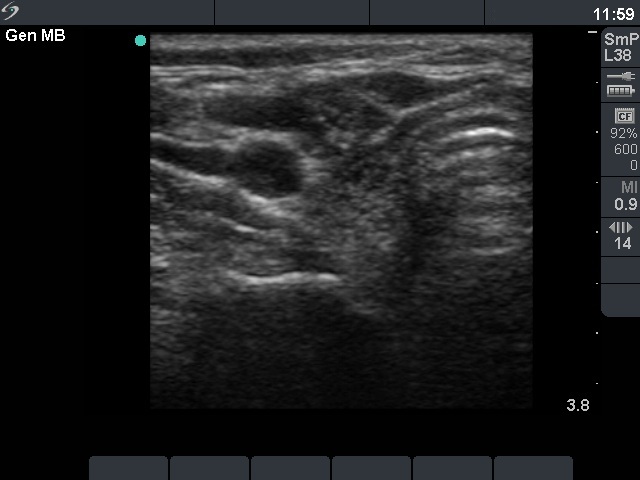

Granulation around surgical thread (histological diagnosis) - case 1386

This is a typical presentation of a granulation around surgical thread: a hypoechogenic, irregularly shaped, avascular mass having several echonormal areas corresponding to a ragged tissue.